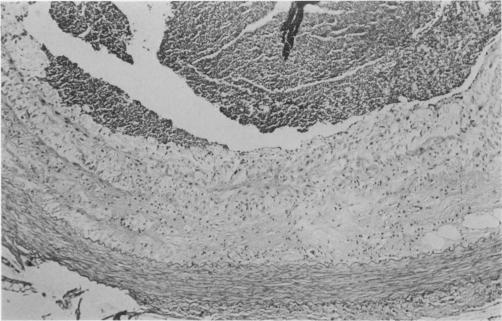

Dutch-Belted rabbits were fed for 18 months an atherogenic semipurified gel diet containing 14% hydrogenated coconut oil and 0.06% cholesterol (approximately 0.15 mg/kcal) or a non-atherogenic basal gel diet containing the same ingredients but with no coconut oil or cholesterol. Rabbits fed atherogenic diet developed hypercholesterolaemia (means 733 mg/dl at 16 months) and plasma lipoprotein (LP) distribution shifted from a pattern in which high-density lipoproteins (HDL) predominated to one in which very-low-density lipoproteins (VLDL) were predominant. Total cholesterol/triglyceride ratio in d less than 1.006 LP changed from 0.3 to 1.8. Plasma cholesterol and LP distribution returned to normal in rabbits fed atherogenic diet for 18 months followed by atherogenic diet plus 3% soya lecithin for an additional 4 months. Rabbits fed atherogenic diet for 18 months had extensive, usually full circumference fibromuscular plaques in main branches of coronary arteries and all portions of aorta which compromised lumen area by almost 50%. These lesions were modified in rabbits fed atherogenic diet plus lecithin. The plaques lacked foam cells and cholesterol clefts, were less cellular with a distinct fibrous surface and occupied less space. Animals fed basal diet did not develop hypercholesterolaemia (means 86 mg/dl at 16 months), although distribution of plasma LP shifted slightly in favour of increased low-density lipoproteins (LDL) and decreased HDL compared with rabbits fed standard commercial diet. Basal diet rabbits had no coronary atherosclerosis and only minimal focal foam cell lesions in proximal aorta. Liver injury including fatty change, cholangitis and portal fibrosis occurred in animals fed atherogenic diet. Thus, rabbits fed appropriate diets low in cholesterol accumulate cholesterol-enriched LP in their plasma and develop lesions in abdominal aorta and main branches of coronary arteries which are similar to those in man. Also, in this experimental model, dietary lecithin promotes a return to normal of the LP distribution profile and removal of lipid from established atherosclerotic plaque.